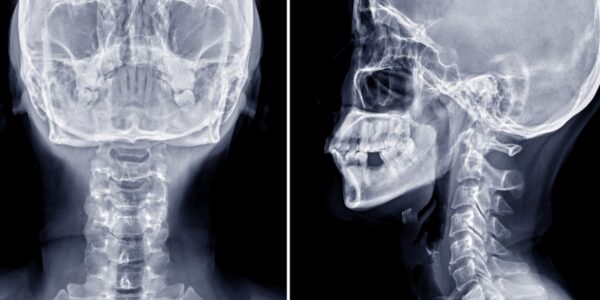

Fatal Cervical Spine Injury Highlights Rare and Catastrophic Workplace Accident

In September 2022, a tragic and medically unprecedented case shook both the orthopedic and workplace safety communities. An 18-year-old laborer in India suffered a catastrophic cervical spine injury when a heavy metallic object fell directly on the front of his…